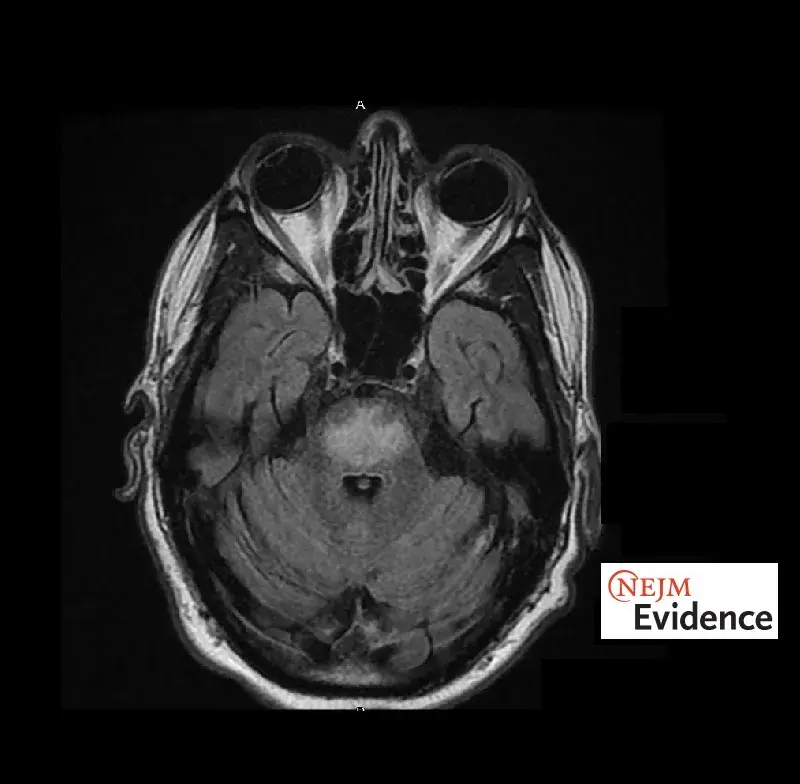

Síndrome da Desmielinização Osmótica: Rara, mas potencialmente grave!

Síndrome da Desmielinização Osmótica: Rara, mas potencialmente grave!